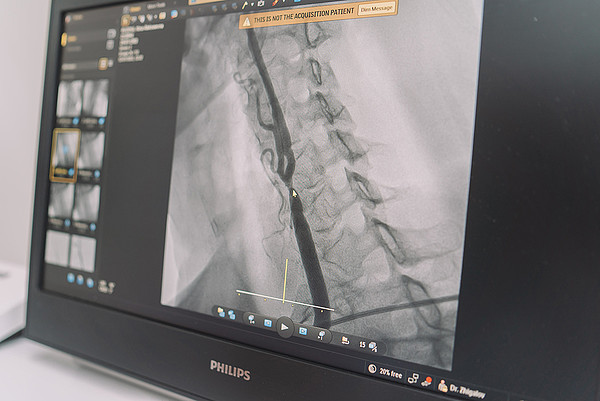

Кировские хирурги провели уникальную операцию при помощи ангиографического комплекса